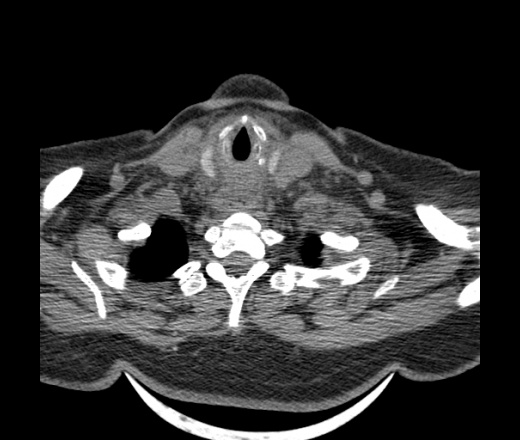

Женщина поступила в х/о спустя 4 дня после того как при употреблении карася подавилась костью.

Наличие газа в средостении на протяжении тел С2-С6 (медиастинальна эмфизема); рыбная кость на уровне тела С6.

Согласен с Вами; конечно, наличие газа в клетчатке ретрофарингеального пространства (затмение с опечаткой..). К сожалению, процесс "продвигается" к медиастиниту. Но почему никто, не отмечает наличие рыб. кости; или это для Всех очевидно?

Так вы уже отметили. Хотя ориентировал бы не скелетотопически, а на перстнечерпаловидный сустав.

Кость то мы сразу выявили, размеры где то 17*2мм, но ее так и не получается найти в этой каше